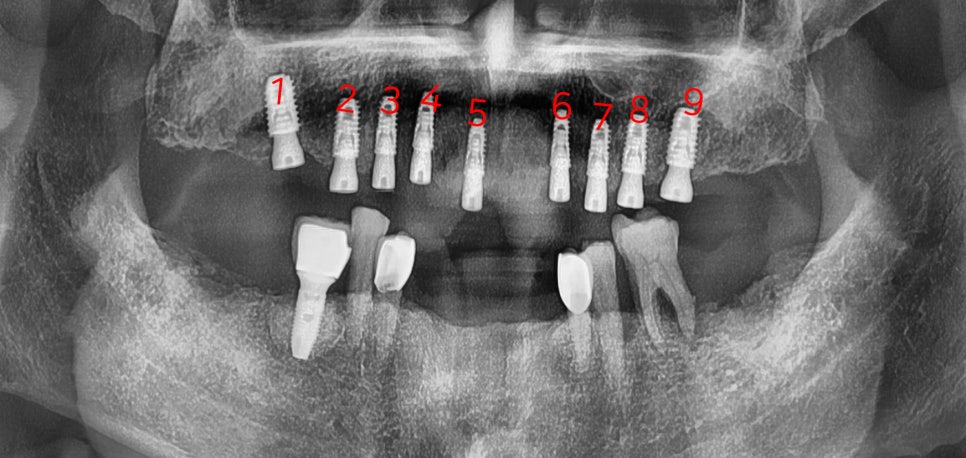

상악 기준으로 권장 개수 는 9개,

하악 기준으로 권장 개수 는 8개 입니다.

각기, 최소 개수 는 상악 7개 / 하악 6개 입니다.

치료 기간 2021.09.18 ~ 2022.02.03